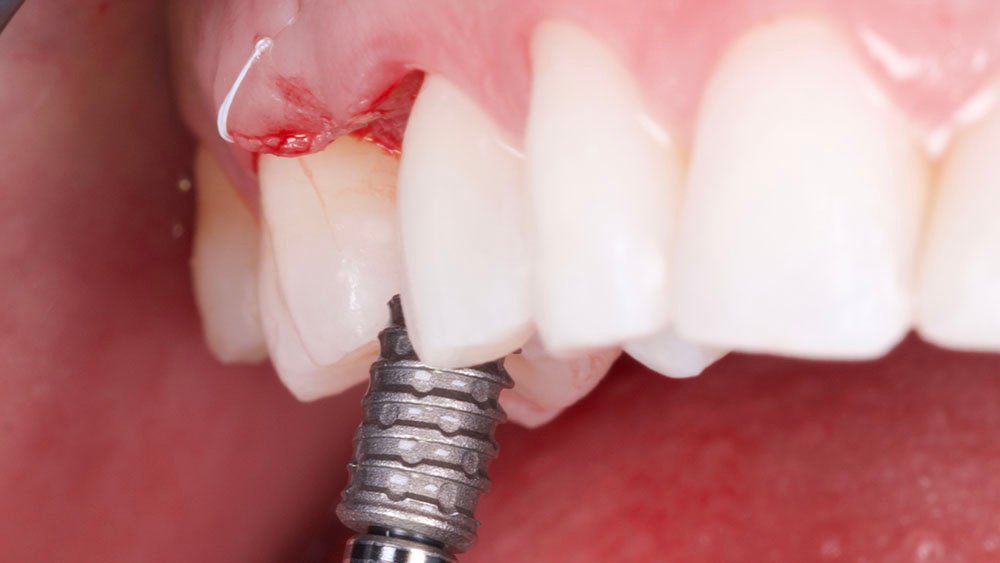

Os nervos alveolares superiores anterior, médio e o palatino maior foram anestesiados com dois tubetes de Cloridrato de Mepivacaína 2% (Cristália Produtos Químicos Farmacêuticos Ltda., São Paulo-Brasil). Com o auxílio de uma lâmina 15C (Syann Morton – Cód.11810 (HOS11810A)), foi realizada uma incisão ligeiramente palatinizada em retalho dividido, paralela ao tecido ósseo palatino, de modo a separar a porção mais epitelial do tecido conjuntivo palatino (aproximadamente 2 mm) da porção mais profunda (aproximadamente 3 mm), para que em seguida, uma segunda incisão no tecido palatino (abaixo do alçapão formado pela primeira incisão) pudesse liberar essa porção mais profunda (juntamente a periósteo) e a mesma seja rotacionada para a vestibular do defeito. Na sequência, outras duas incisões em retalho total (até periósteo) foram realizadas de modo a dar a forma das futuras papilas proximais. Uma última incisão superficial foi realizada na porção oclusal do defeito com a finalidade de desepitelização para que o tecido oclusal também fosse rotacionando para a vestibular. Para o descolamento do enxerto e mucosa vestibular foram utilizadas curetas Molt (Supremo Instrumentais).

Confeccionou-se um dente provisório aparafusado com coifa de titânio 4,5 x 4 mm – Linha Ideale (Implacil De Bortoli, São Paulo-Brasil), sobre o Pilar Ideale 4,5 x 4 x 2,5 (Implacil De Bortoli, São Paulo-Brasil), apoiado no Implante Maestro 4 x 11 (Implacil De Bortoli, São Paulo-Brasil), obtendo um torque aproximado de 40N. E por fim, realizou-se a proservação e acompanhamento radiográfico.